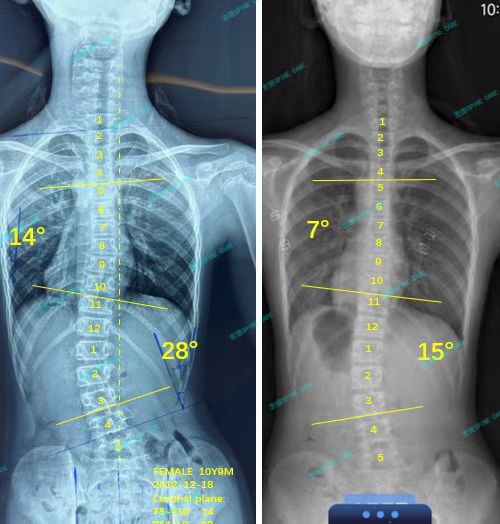

我是甜甜,28度到15度,我做到了~

案例主人:甜甜 发现侧弯年龄:13岁 侧弯情况:Cobb角度28度

我在这里开始了我的康复之旅,每天坚持训练,还按照杨博士的建议戴上了支具。时间过得真快,转眼两年过去了,最近我脱掉支具去拍片,结果简直太棒了!我的28度腰弯降到了15度,胸弯也从14度降到了7度。

I started my recovery journey here, training every day and wearing braces as recommended by Dr. Yang. Time flies so fast. Two years have passed in the blink of an eye. Recently, I took off my braces to take a photo shoot, and the results were amazing! My 28-degree waist bend dropped to 15 degrees, and my chest bend dropped from 14 degrees to 7 degrees.